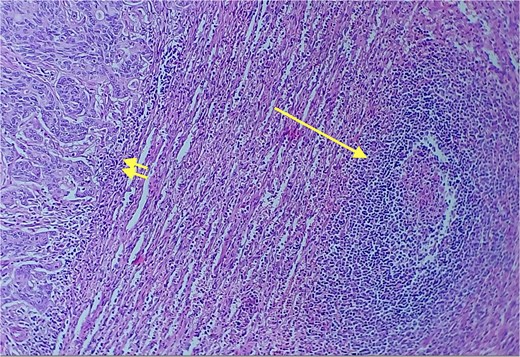

Given the histopathological findings, a laparoscopic splenectomy was performed in a second operative session. The procedure was carried out in the left lateral decubitus position using three trocars. Intraoperatively, a 3 × 3 cm lesion was identified within the splenic parenchyma. The specimen (Fig. 6) was extracted through the previously used Pfannenstiel incision. Histopathological analysis confirmed infiltration by an enteric-type adenocarcinoma (Figs 7–9).

Area of enteric-type adenocarcinoma composed of neoplastic proliferation of columnar epithelial cells with nuclear atypia, eosinophilic cytoplasm, and a complex tubular and cribriform arrangement with endoluminal necrosis (arrows); H&E ×200.